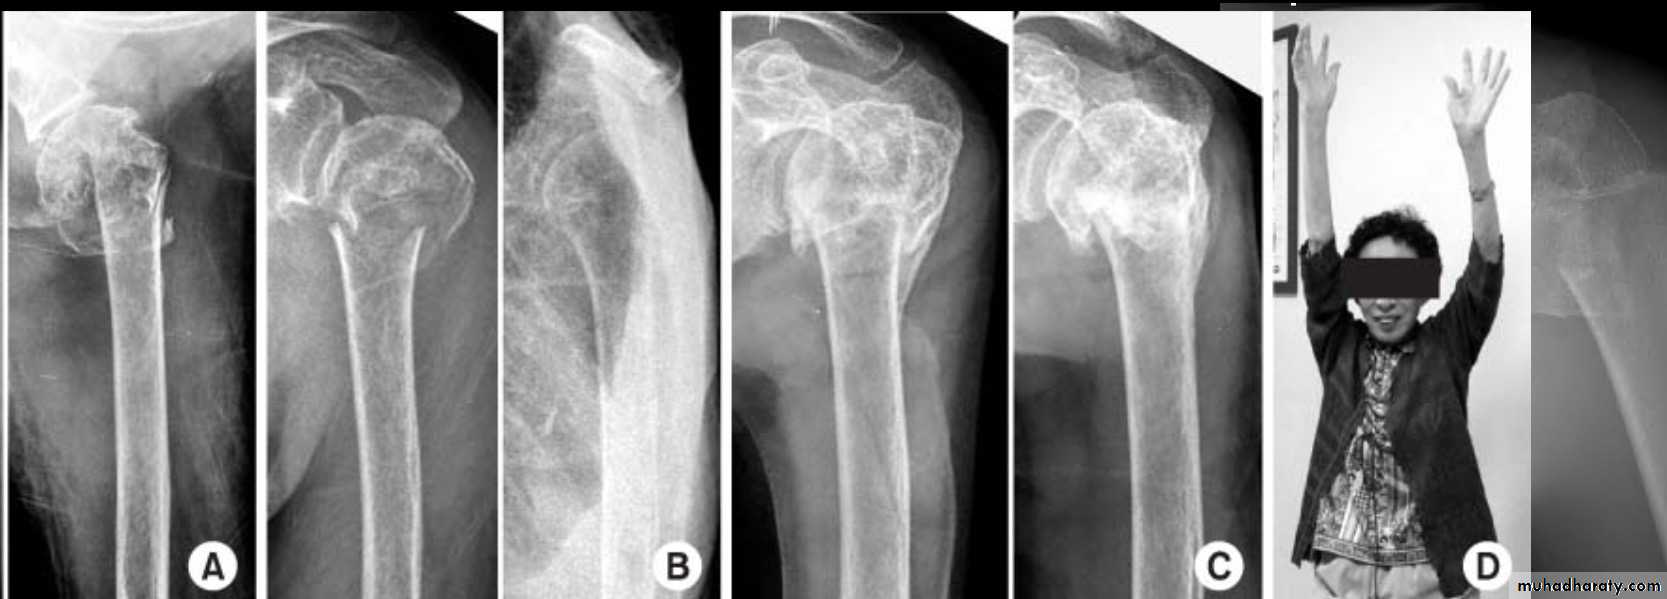

Three part fracture

Its account for 5%of proximal

Humeral fracture

Fracture line involve 3_4 part

Two part are displaced more than

1cm

Or more than 45 degrees

TREATMENT

30

ORIF